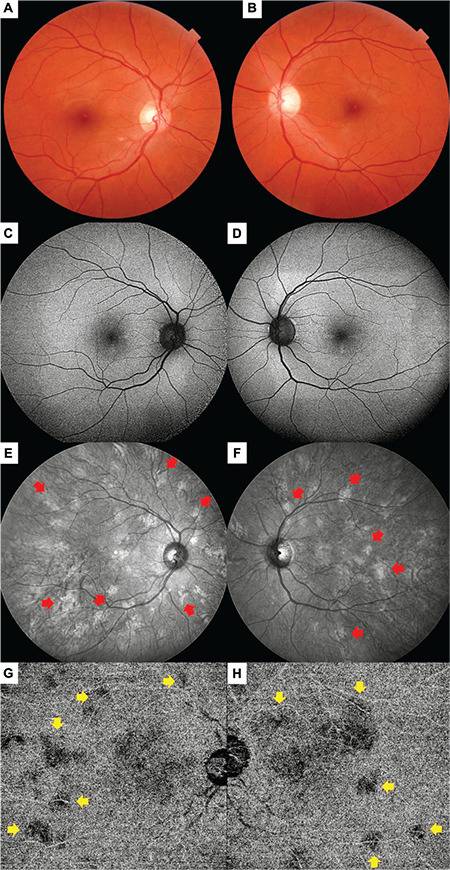

Objectives: Yasunari nodules are choroidal lesions observed in patients diagnosed with neurofibromatosis type 1 (NF-1) and characterized by relatively irregular dome-shaped, plaque-like, or patchy boundaries. The present study examines the multimodal imaging characteristics of Yasunari nodules and their value in the diagnosis of NF-1.

Materials and methods: Medical records including optical coherence tomography (OCT), enhanced depth imaging OCT, infrared reflectance (IR) imaging, OCT angiography, and color fundus images of NF-1 patients who were examined at the Department of Ophthalmology in Dokuz Eylül University Faculty of Medicine between January 2022 and December 2023 were retrospectively reviewed for the presence of Yasunari nodules.

Results: A total of 54 eyes of 27 patients were included in the study. At least one choroidal nodule was detected on IR imaging in 52 eyes (96.3%). In 31 (72.1%) of the 43 eyes (79.6%) with available high-quality OCT angiography images, choroidal nodules were observed as areas showing a flow deficit in the choriocapillaris layer. Of the total 54 eyes included, Lisch nodules without choroidal nodules were observed in 2 eyes (3.7%). In 16 eyes (29.6%), Lisch nodules were not detected despite the presence of choroidal nodules. Both Lisch nodules and choroidal nodules were detected in the other 36 eyes (66.7%).

Conclusion: Yasunari nodules are frequently observed in NF-1 cases and can be easily detected with multimodal imaging techniques, especially IR imaging. The ability to visualize choroidal nodules before the appearance of Lisch nodules demonstrates the importance of Yasunari nodules in the diagnosis of NF-1.